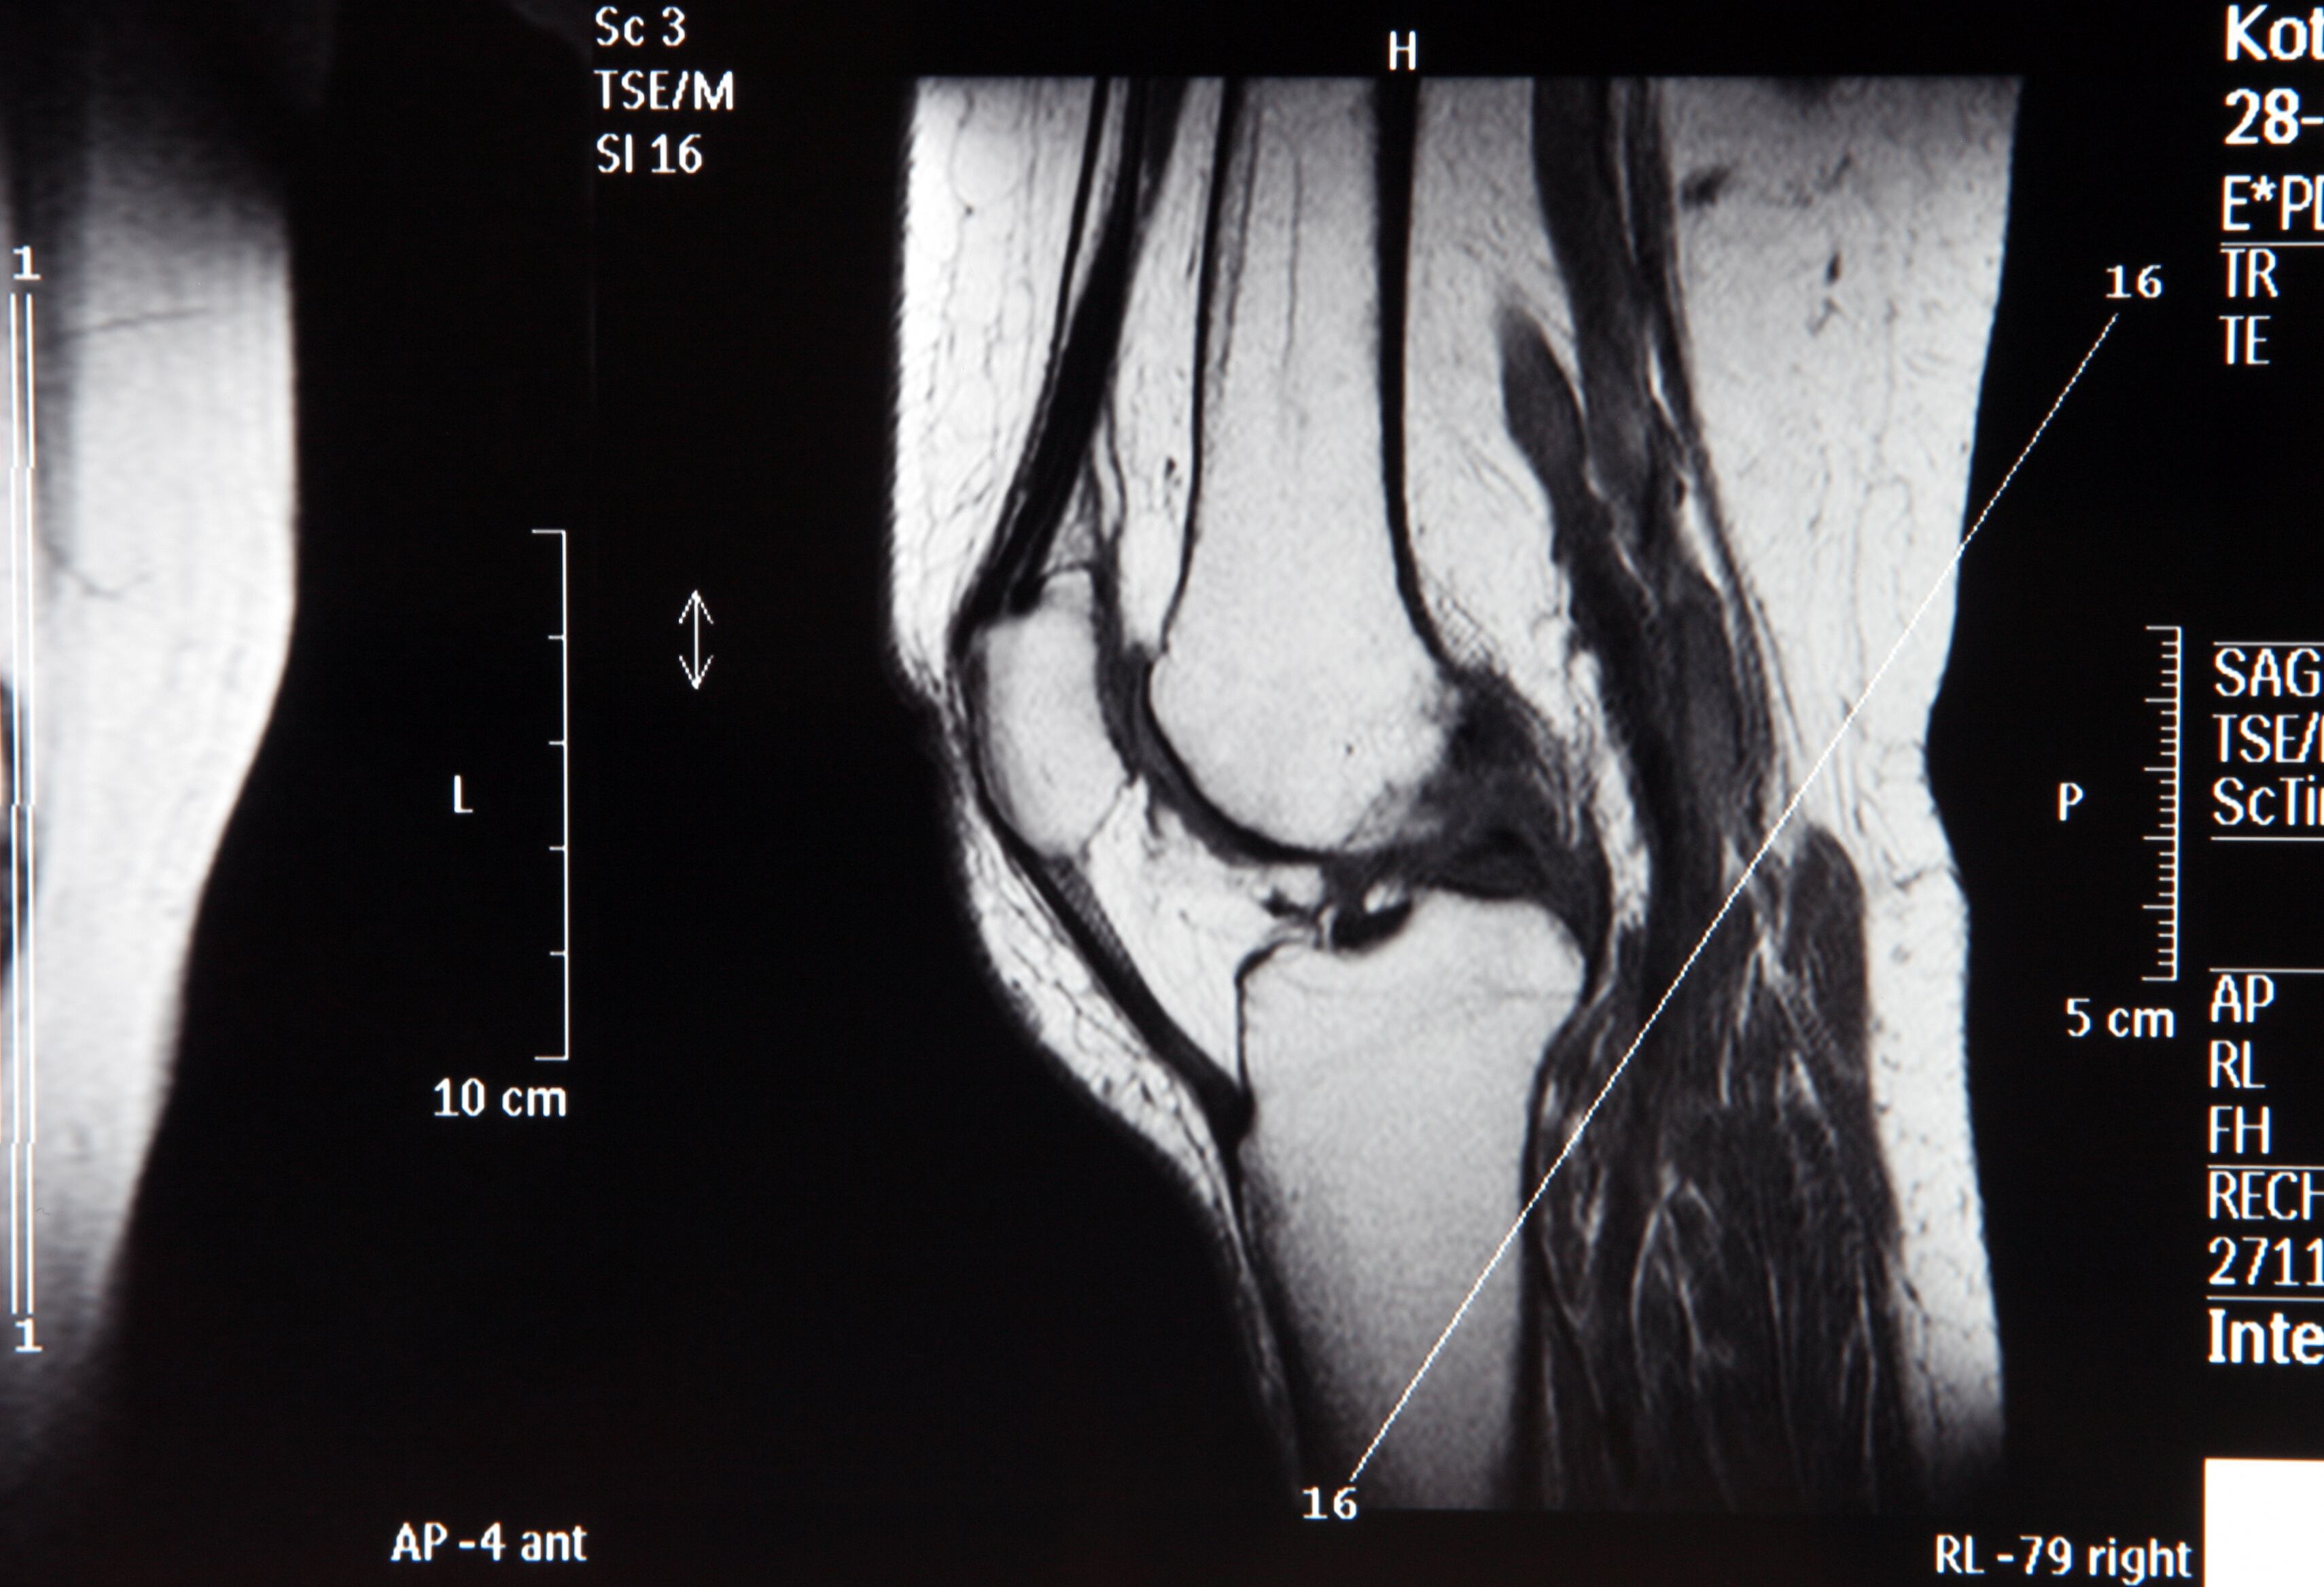

Radiografía del hueso de la rodilla.

El diagnóstico de cáncer óseo suele implicar una combinación de pruebas, como radiografías, tomografías computarizadas (TC), resonancias magnéticas (RM) y biopsias. Foto: Getty Images

El diagnóstico de cáncer óseo suele implicar una combinación de pruebas, como radiografías, tomografías computarizadas (TC), resonancias magnéticas (RM) y biopsias. Según el NCI, una biopsia, en la que se extrae una muestra de tejido para examinarla bajo un microscopio, es esencial para confirmar la presencia de células cancerosas y determinar el tipo exacto de tumor.